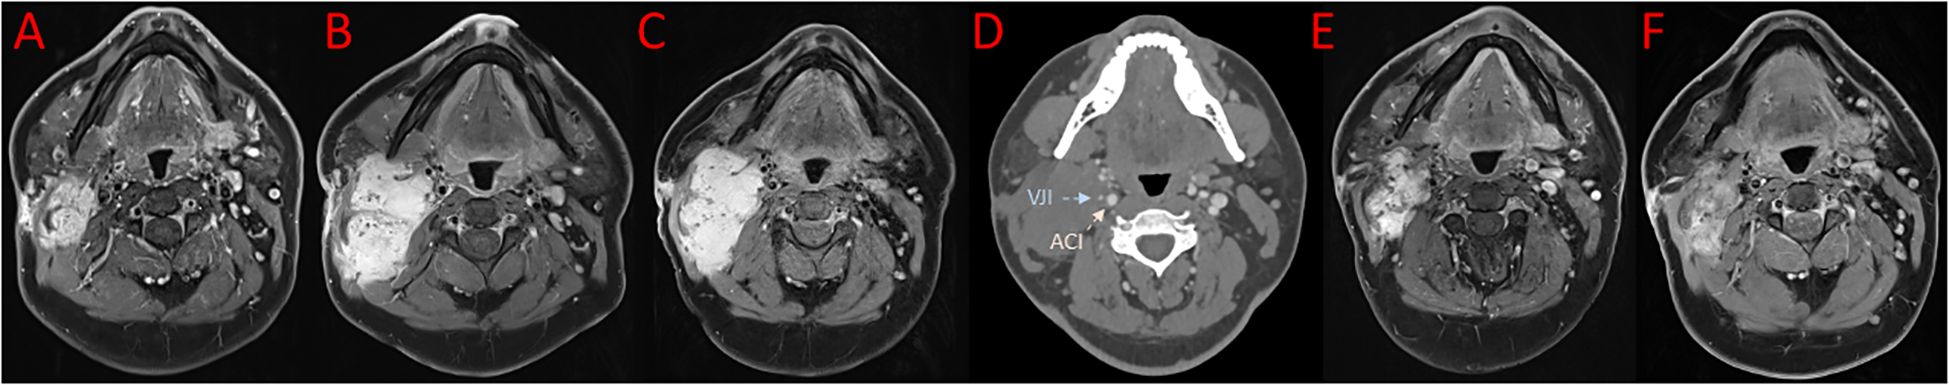

A 29-year-old patient reported a progressively growing indolent tumor below the right mastoid. Ultrasound and MRI-imaging revealed a 26 mm x 35 mm x 40 mm mass adjacent to the right parotid gland with dorsal sound extinction and enlarged cervical lymph nodes. On the suspicion of neoplasia, the tumor was surgically excised at a community hospital. Histopathological examination revealed a DT with a microscopically positive resection margin (R1 resection). MRI-imaging conduced six months later as part of the regular follow-up showed an extensive mass interposed between the right sternocleidomastoid muscle and the carotid sheath, suggesting early recurrence of the DT (Figure 1A), and the patient was referred to our university sarcoma centre. The patient was in good general condition, reporting only a localized sensation of tension in the right cervical region. Owing to size and infiltration into the carotid sheath, the recurrent DT was deemed unresectable, and preparations for systemic treatment were initiated. Against the backdrop of a previous history of hereditary severe precapillary pulmonary hypertension (BMPR-2 mutation), first-line treatment with PLD (40mg/m2 intravenously every 4 weeks) was initiated due to the improved toxicity profile. However, on account of repeated severe allergic infusion reactions despite prophylactic treatment with high-dose dexamethasone and histamine receptor antagonists, treatment with PLD had to be aborted prematurely after two cycles. Next, oral treatment with the TKI sorafenib (400mg daily orally) was started. Nevertheless, MRI-imaging performed two months into sorafenib treatment demonstrated progression of the DT with compression of the right internal jugular vein, and imminent infiltration of the right carotid artery (Figure 1B). At this point, the patient remained in good general condition; however, he reported progressive swelling in the right facial region. Given the proximity to the carotid artery and corresponding life-threatening implications, treatment was switched to doxorubicin in combination with dacarbazine, irrespective of pulmonary hypertension. After three cycles of chemotherapy, which were well tolerated without impairment of ventricular function, MRI-imaging once again indicated progression of the DT with now full compression of the right internal jugular vein and imminent contact to the right carotid artery (Figure 1C). Clinically, the patient reported a progressive sensation of tension on the right side of his neck, accompanied by increasing swelling in the right facial region. Corroboration for the risk of a pending life-threatening arrosion of the right carotid artery was provided by Doppler ultrasound and CT-angiography (Figure 1D). Due to the highly refractory growth pattern, usually uncommon for DT, another biopsy was taken and subsequent histopathological examination reconfirmed the diagnosis of a DT with characteristic aberrant nuclear expression of ß-catenin (Figure 2). To explore potential therapeutic targets, an additional biopsy was subjected to whole-genome sequencing. This analysis revealed a CTNNB1 mutation characteristic of desmoid-type fibromatosis (c.134C>T, p.S45F), which is recognized as an independent adverse prognostic factor. No actionable therapeutic targets were identified. On the cusp of an imminent life-threatening arrosion of the right carotid artery, therapy was started with the oral FDA-approved selective γ-secretase inhibitor nirogacestat (150 mg twice daily). With EMA approval still pending at that time, nirogacestat was administered within a compassionate use program (CUP). MRI-imaging conducted at four and seven months after initiating nirogacestat therapy revealed a sizable regression of the DT without any further direct contact to the carotid sheath (Figures 1E, F). All previously reported symptoms had fully resolved. No significant side effects were observed by treatment with nirogacestat. As of now, treatment with nirogacestat is intended until disease progression. A schematic portrayal summarizing the different treatments in chronological order is shown in Figure 3.

Figure 1. Images in axial reconstruction at different timepoints. (A) MRI imaging showing early recurrence of desmoid tumor after surgery. (B) MRI imaging two months into sorafenib treatment. (C) MRI imaging after three cycles of doxorubicin in combination with dacarbazine. (D) Corresponding CT-scan revealing full compression of the right internal jugular vein (VJI, blue arrow) and imminent contact to the right carotid artery (ACI red arrow). MRI imaging after four (E) and seven (F) months of nirogacestat treatment.